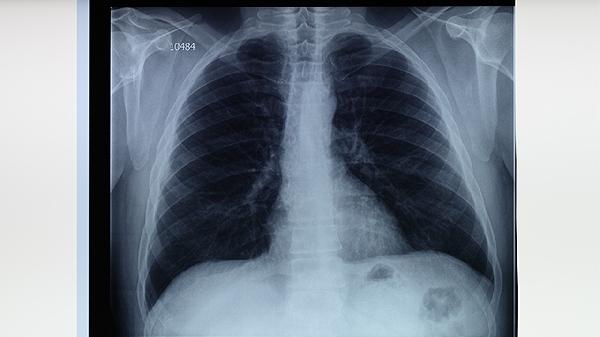

完成全程治疗后仍需定期复查胸部影像学,观察病灶吸收情况。日常生活中需注意保持居室通风,咳嗽时掩住口鼻,痰液需消毒处理。饮食应保证优质蛋白和维生素摄入,避免酒精减轻肝脏负担。密切接触者应进行结核菌素试验筛查,实现早发现早治疗。